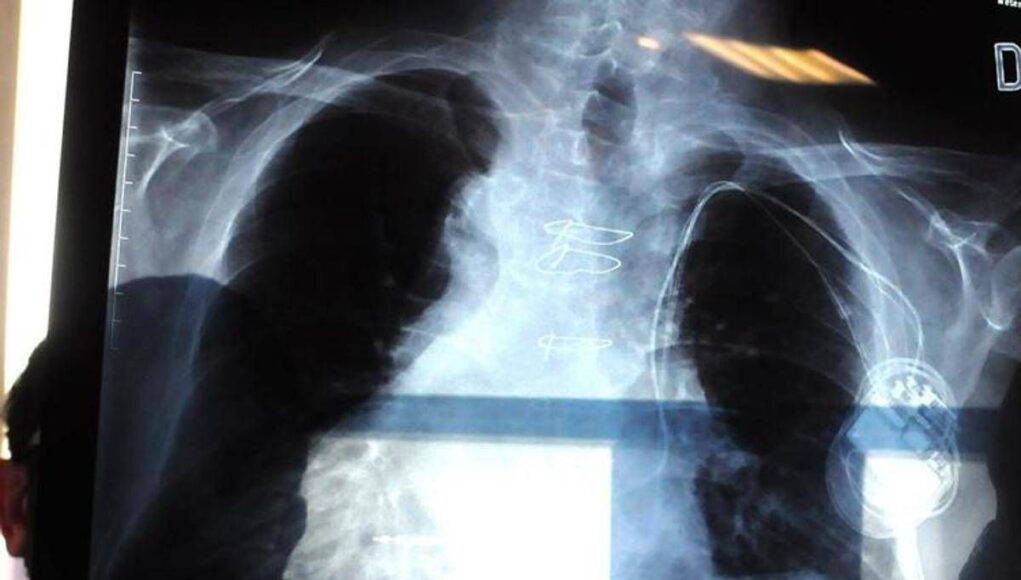

La polmonite, prosegue il presidente di Aipo, è un’infezione che “può essere localizzata in un punto particolare del polmone. L’ente patogeno più frequente in questo caso è lo pneumococco, contro il quale esiste appunto una vaccinazione. Esistono poi le polmoniti interstiziali che colpiscono il tessuto connettivo del polmone, l’area dove avviene lo scambio, per questo l’infezione può essere molto diffusa e anche bilaterale. E’ dovuta prevalentemente a virus, il Covid tra questi, come abbiamo visto durante la pandemia, e ad alcuni batteri. Altro caso abbastanza emblematico è la legionella, oppure i cosiddetti agenti intracellulari, micoplasma e clamidia”. L’intestizio, precisa Micheletto, “è il tessuto di sostegno del polmone, dove avviene il passaggio dell’ossigeno e dell’anidride carbonica nel senso contrario, tra gli alveoli e i capillari. Quando questo interstizio viene colpito, lo scambio viene notevolmente ridotto. Ma se il paziente ha la bronchite cronica o è un fumatore, questi spazi sono già compromessi. E quindi può dare casi gravi”.

Ma quali sono i segnali d’allarme che indicano una possibile polmonite? “Una polmonite si presenta prevalentemente tosse e febbre”, descrive lo pneumologo. Ma la “gravità che causa ospedalizzazione riguarda la difficoltà respiratoria, che può essere altamente rischiosa”, conclude.